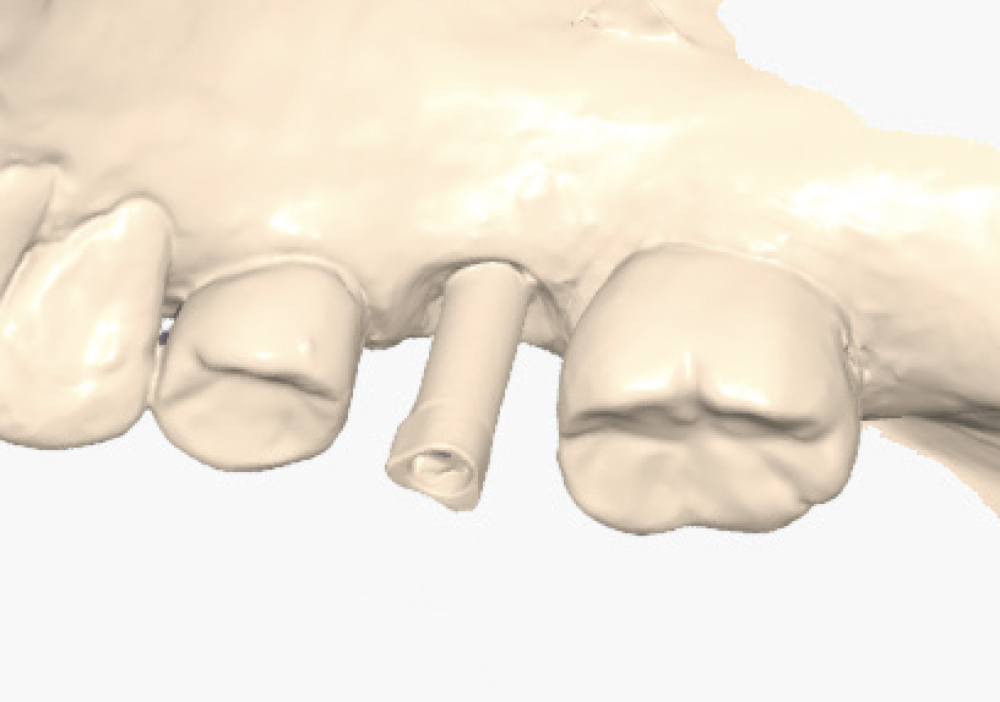

Implant post scan on left side of mouth

Implant post scan pointing down

Implant post scan close up